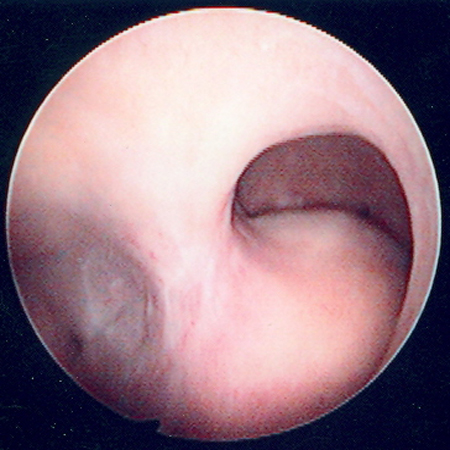

Multiple polyps are identified on hysteroscopic examination of the uterine cavity in this patient with persistent vaginal spotting

From the personal collection of Dr M.F. Mitwally and Dr R.J. Fischer; used with permission